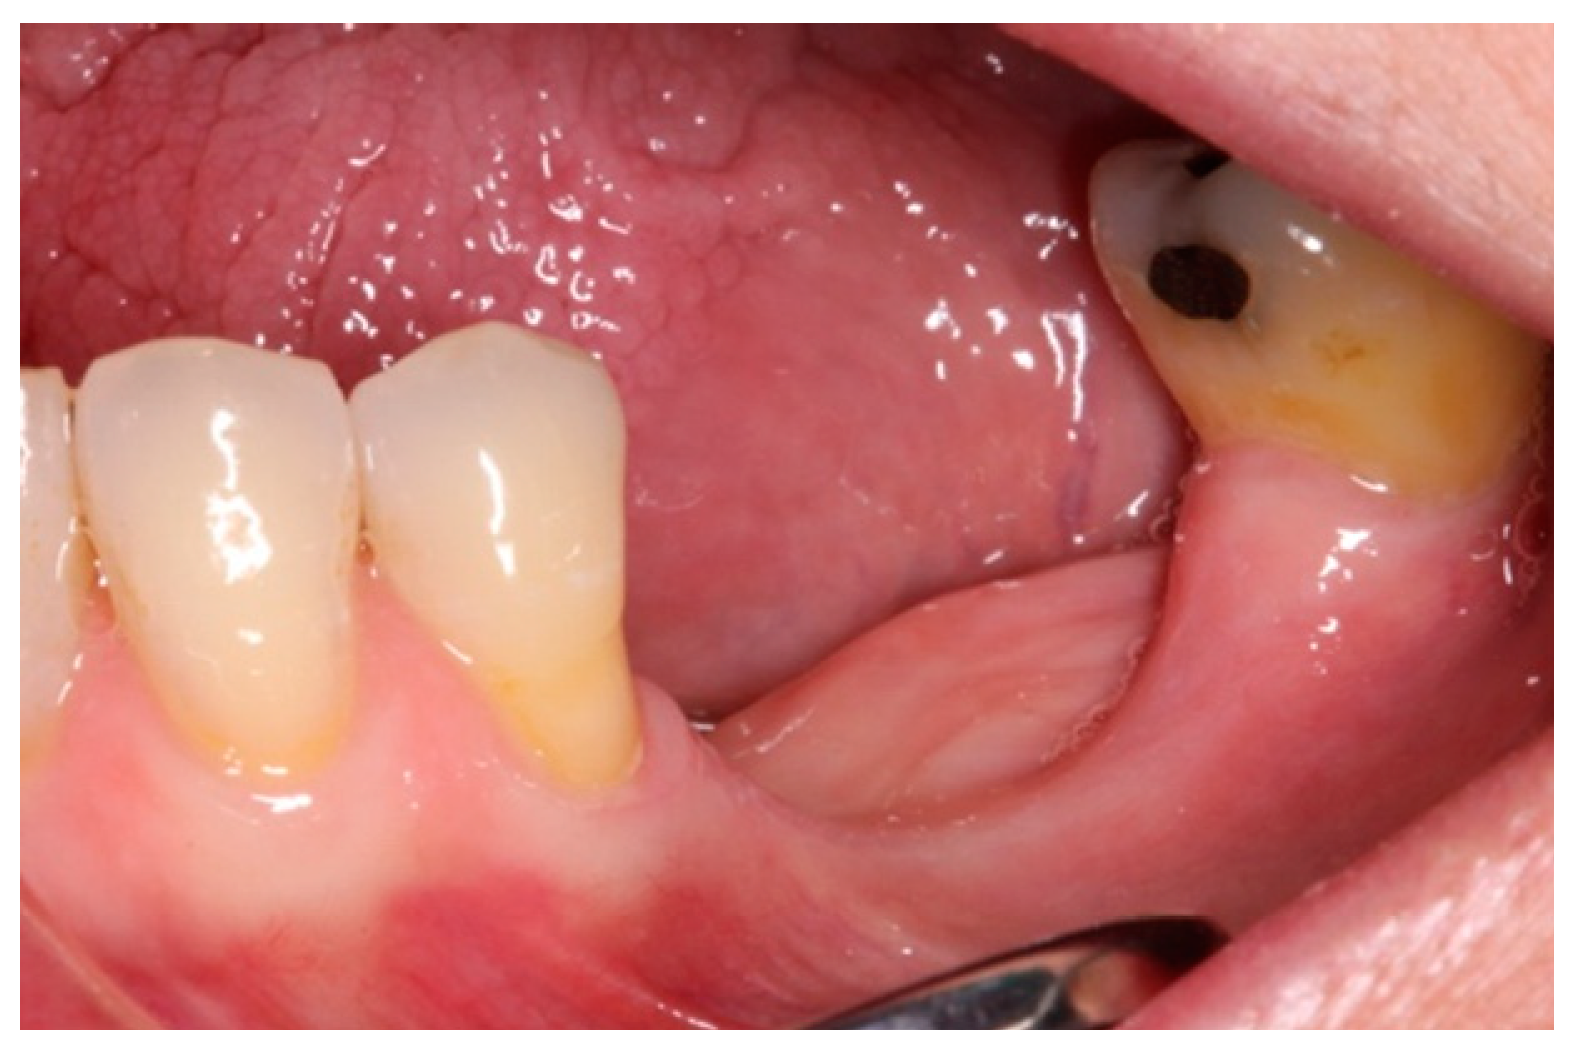

3. Case Report and Results

- First surgery: Local anesthesia Articaine 4% with epinephrine (1:100,000) was administered. An intrasulcular incision was made from the mesial of 3.3 to the distal of 3.7, continuing along the anterior border of the external ramus of the mandible. Periosteal incisions were made to mobilize the vestibular flap and the upper fibers of the mylohyoid muscle were disinserted to passivate the lingual flap and thus obtain a tension-free closure (Figure 3). We then checked the position of the mesh and proceeded to collect bone from the ascending branch using the bone scraper (Micross®, Selecdent, Barcelona, Spain) (Figure 4A). Cortical perforations were made to promote bleeding (Figure 4B). We mixed the autologous bone with the xenograft (Tioss®, Sanhigia, Bujaraloz, Spain) in a 70:30 ratio, inserted it into the mesh, and the mesh was placed in the defect.